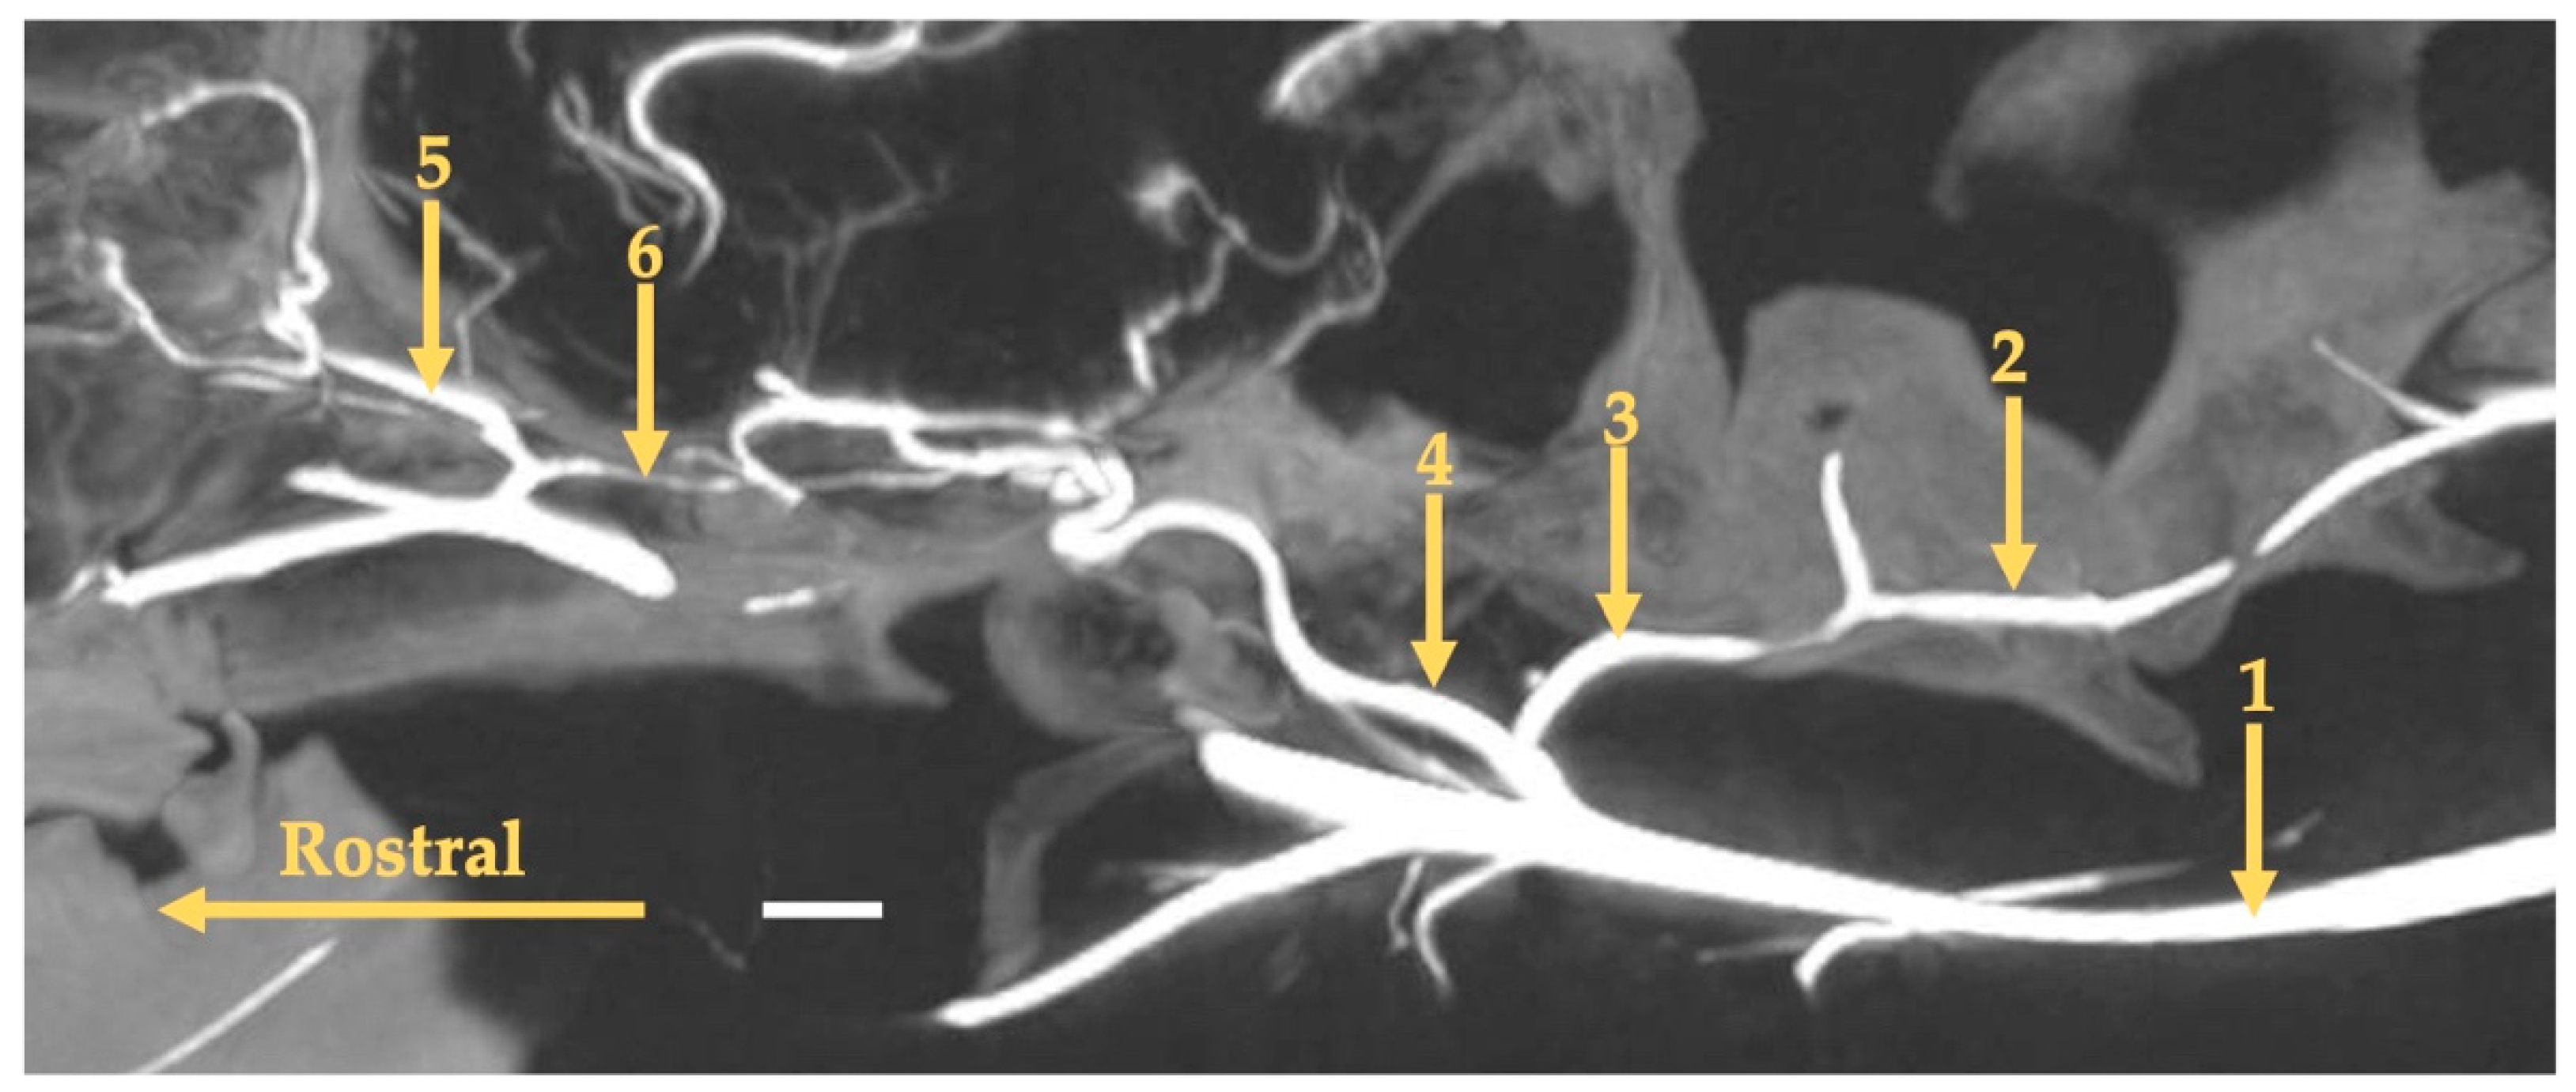

3. Results